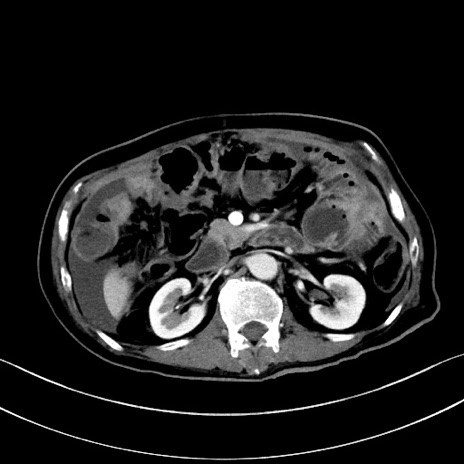

症例28(横断像)

【症例】60歳代男性

【主訴】嘔吐

【現病歴】胃癌にて胃全摘後。食思不振が悪化し、夜中に嘔吐することがある。

【既往歴】胃癌、胃全摘、脾摘、胆摘後

【データ】WBC 5900、CRP 10.56